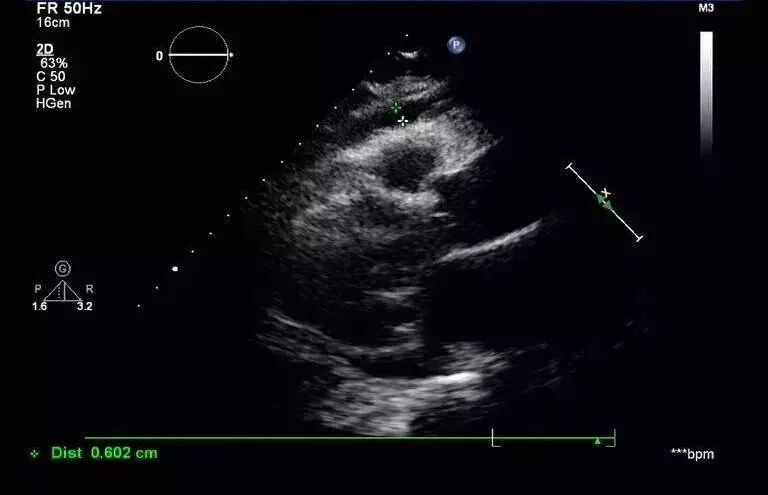

(图5)

图5: 2017年8月30日复查经胸超声心动图提示:左室靠近心尖处血肿形成。少量心包积液。左室靠近心尖处外壁可见一低回声包块,大小约40mmx21mm,边界尚清。